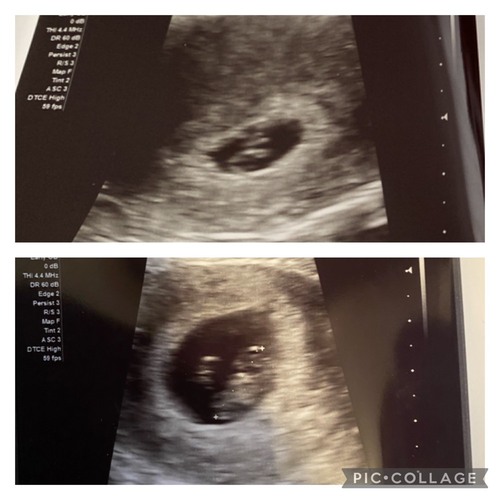

Ik was al verder dan gedacht en met 9+4 te laat voor de theorie, maar je ziet hier wel 2 lichte plekken en in het echt is het nog een stuk duidelijker verschil. Die langrekte witte streep links/onder bij de baby is waar je dan op hoort te letten. (Dit was bij mij uitwendig. En als het dus optijd zou zijn was het een jongen volgens de theorie.)